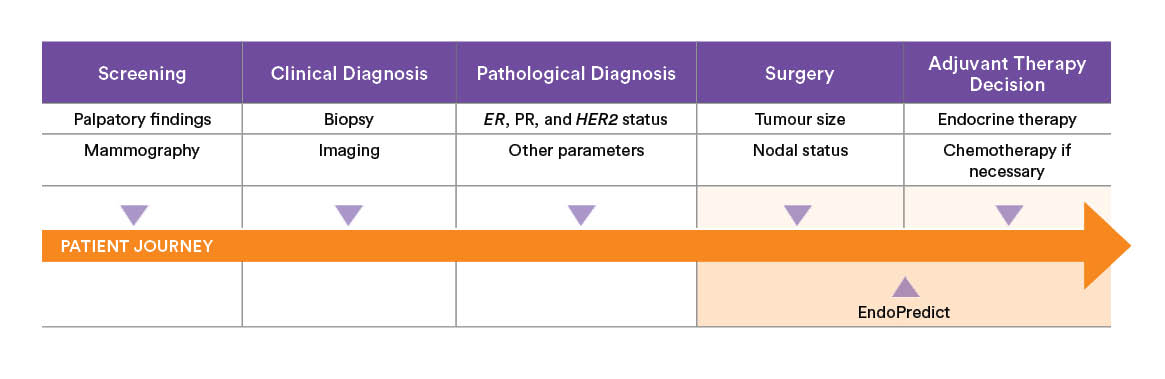

When to use EndoPredict?